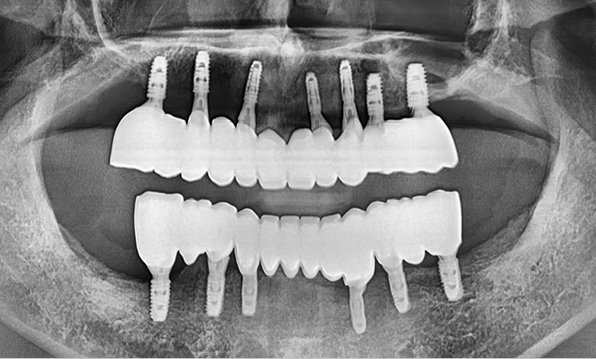

전체 임플란트

위 아래 치아가 정확하게 맞아야하는 고난이도 임플란트

임상 경험이 많은 숙련된 전문의의 섬세한 기술력이 중요합니다.

정확성 높은 식립의 노하우

3D 디지털 진단을 통한 체계적인 계획

전체 임플란트는 위턱과 아래턱의 교합, 잇몸뼈의 상태 및

얼굴 변화 등 모든 것을 고려해 식립해야 합니다.

서울더자연치과는 3D 디지털 기술의 정밀 진단을 바탕으로

수술 계획을 세워 수술을 집도합니다.

치료기간 : 2021.04.12~2021.09.15